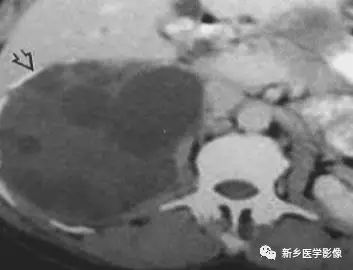

主要包括合并钙化的感染性病变及肿瘤性病变,如: 肾上腺囊肿,肾上腺癌,嗜铬细胞瘤